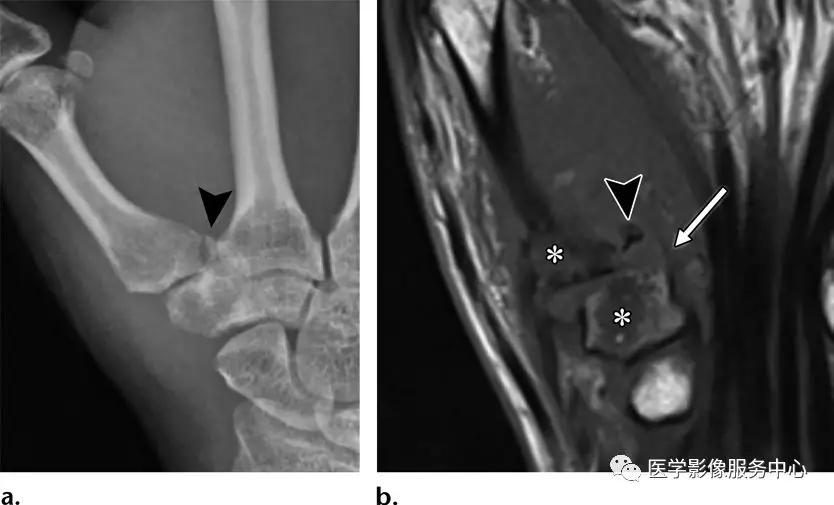

Bennett骨折:第一掌骨底部的关节内骨折,小撕脱骨片铆钉于大多角骨。

反Bennett骨折:

第五掌骨桡侧基底部的略示移位的关节内骨折。由于尺侧腕伸肌腱的反作用牵拉力,第五掌骨向近端及尺侧移位。